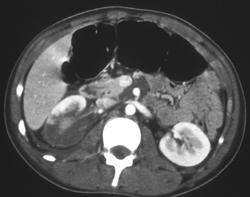

Polycystic Liver and Renal Disease